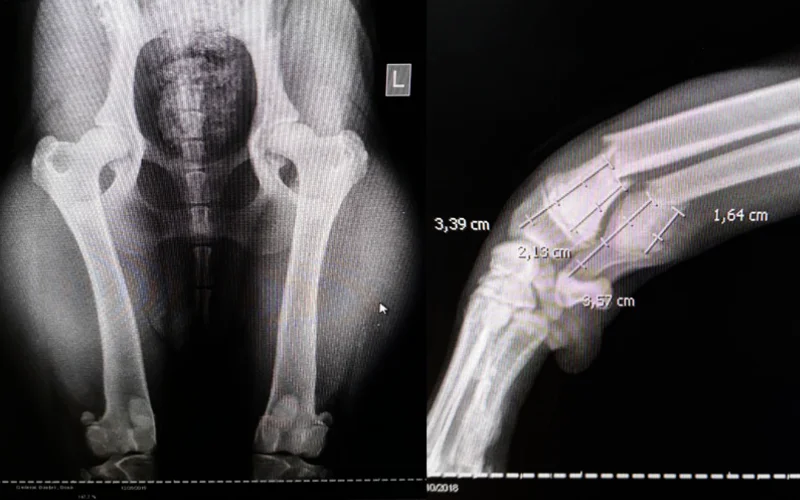

Savremenu veterinarsku medicinu danas je nemoguće zamisliti bez kvalitetne radiološke, odnosno rendgenske dijagnostike. Ona nam svakodnevno omogućava postavljanje precizne kliničke dijagnoze za gotovo sva oboljenja. Visoki kvalitet rendgenskog snimka i visoka stručnost veterinara koji ga procenjuje su od presudnog značaja za kvalitetan medicinski tretman.

Radiološka dijagnostika, odnosno rendgenski pregled ljubimaca je veoma svestran, učinkovit i vrijedan alat u veterinarskoj medicini koji se koristi u raznim područjima dijagnostike. Od pregleda mišićno-koštanog sistema, preko dijagnosticiranja plućnih ili srčanih bolesti do otkrivanja začepljenja crijeva kod ljubimaca ili problema sa kostima, zglobovima i kičmom. Rendgenske snimke zbog toga veterinarima pružaju mogućnost za veoma preciznu i brzu dijagnozu. Vet Centar nudi mogućnost pregleda na nekim od trenutno nasavremenijih aparata za radiološku dijagnostiku.